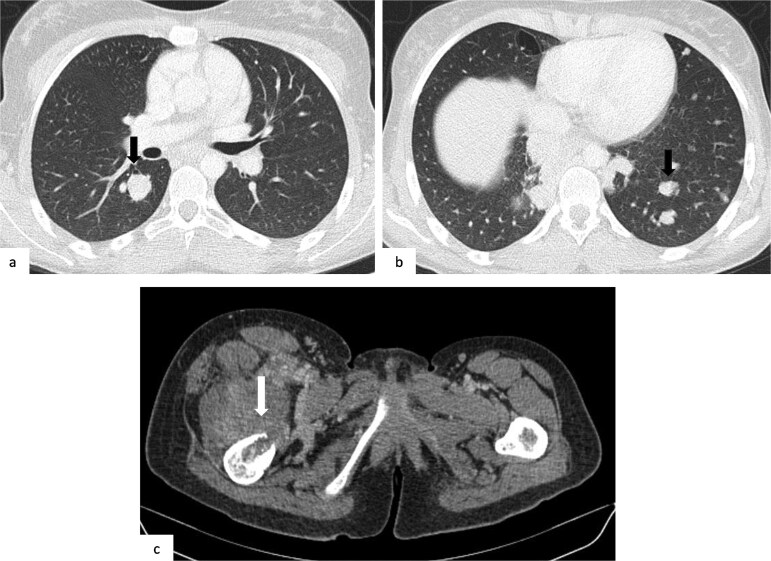

骨肉瘤是儿童和青少年中最常见的恶性骨肿瘤,以长骨为主,常发生肺转移。脑转移是罕见的,发生在1.8%至5.6%的病例中,出血性转移非常罕见,文献中只有少数病例记录。我们报告的情况下,一个16岁的女孩谁提出急性头痛和癫痫发作。影像显示出出血性脑和肺转移,活检证实为原发性股骨骨肉瘤。本病例是一种罕见的骨肉瘤,并突出了其侵袭性转移行为。

Osteosarcoma is the most common malignant bone tumor in children and adolescents, with a predilection for long bones and frequent pulmonary metastases. Brain metastases are rare, occurring in 1.8% to 5.6% of cases, and hemorrhagic ones are exceptionally uncommon, with only a few cases documented in the literature. We report the case of a 16-year-old girl who presented with acute headache and seizures. Imaging revealed hemorrhagic brain and pulmonary metastases, and biopsy confirmed a primary femoral osteosarcoma. This case represents an exceptionally rare presentation of osteosarcoma and highlights its aggressive metastatic behavior.